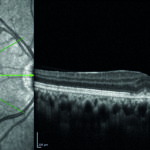

Neovascolarizzazioni coroideali nelle infiammazioni oculari